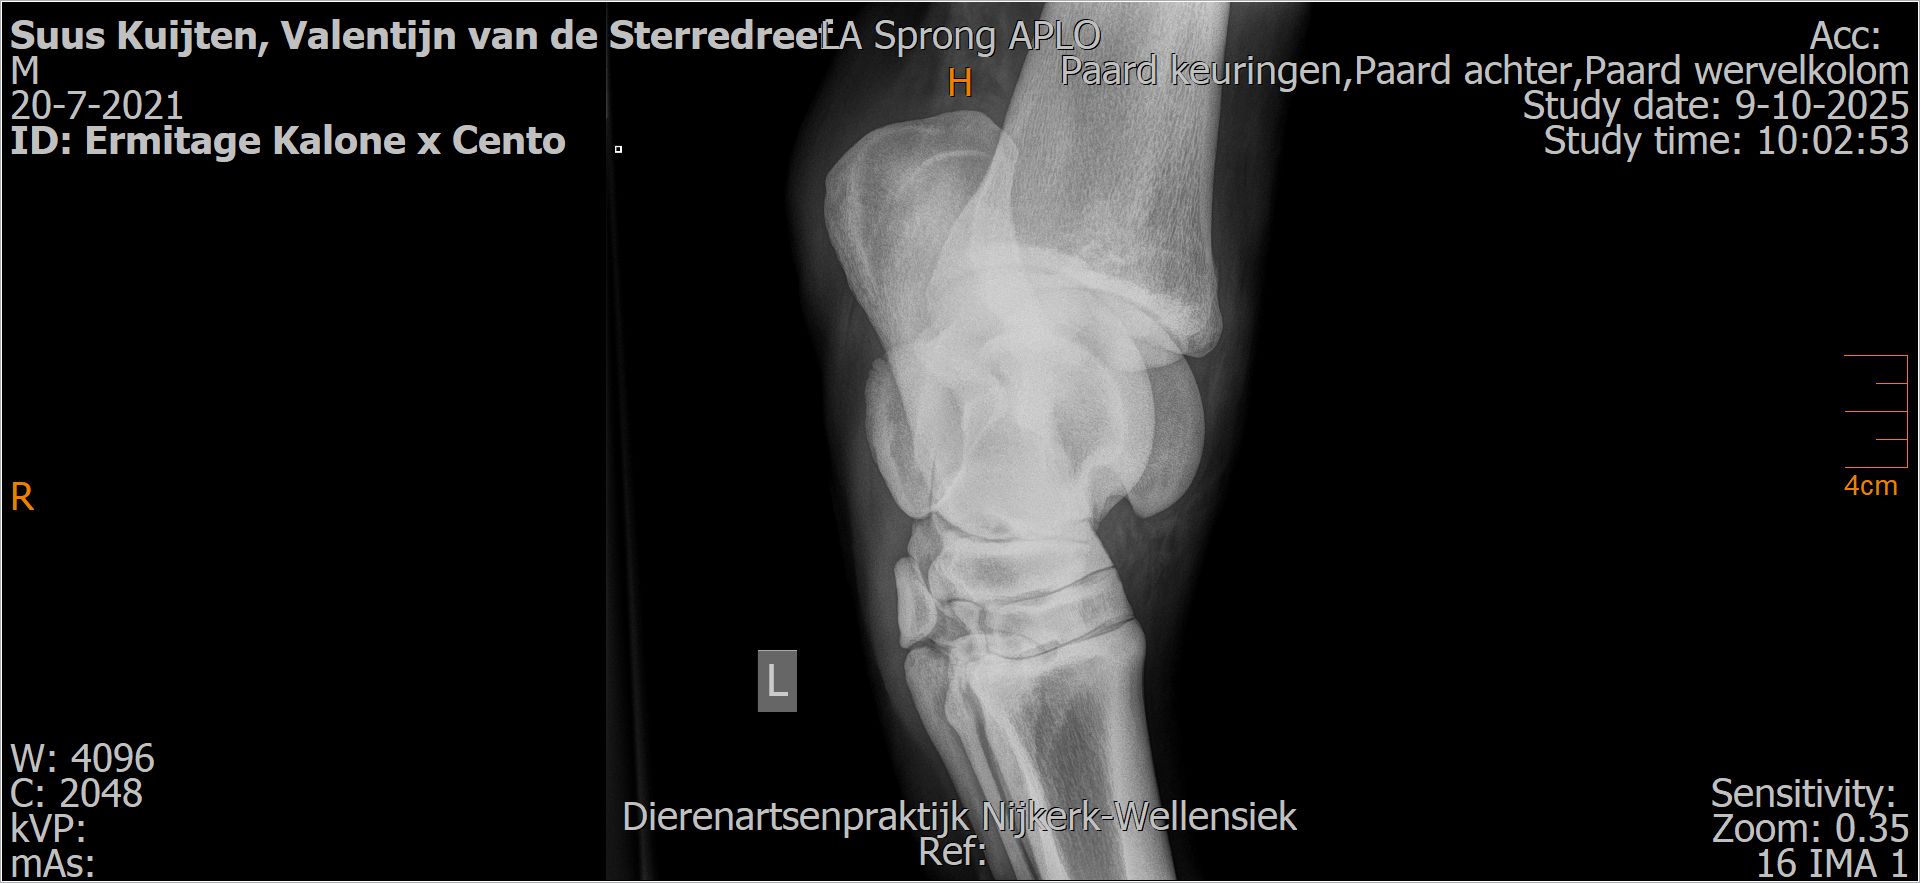

Valentijn van de Sterredreef

Leeftijd:

4

Röntgenfoto’s